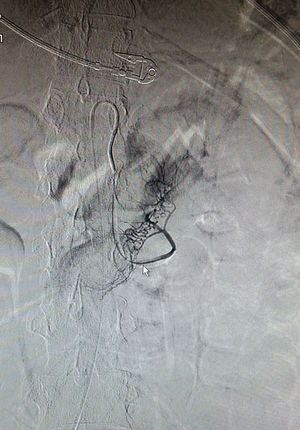

Case 1A 30-year-old woman having been diagnosed 5 years earlier with distal UC was being treated with mesalazine and azathioprine started due to cortico-dependence 4 years later. She was admitted to our unit, having been referred from another centre due to a severe cortico-refractory flare-up associated with fever and leukopenia. On admission, the patient was having 15 bowel movements per day with traces of blood, and pain in her left flank. Laboratory testing revealed pancytopenia (haemoglobin 7.3g/dl, neutrophils 600 × 106/l, platelets 102,000 × 106/l), hypoalbuminaemia (23.6g/l), elevated acute phase reactants (C-reactive protein [CRP] 123mg/dl and faecal calprotectin 4236mg/kg) and a normal liver panel. Rectoscopy showed an erythematous mucosa with deep “geographic” ulcers. These ulcers were biopsied. As CMV infection was strongly suspected, treatment was started with intravenous cyclosporine and ganciclovir. Transfusion support, colony-stimulating factor, antibiotic coverage and enteral nutrition were started as well. CMV serology was negative for IgG and positive for IgM, with a viral load (VL) of 16,923copies, and the rectal biopsies revealed CMV through immunohistochemistry, thereby confirming a diagnosis of primary CMV infection affecting the bowel. Chorioretinitis and HIV infection were ruled out. Given the persistence of fever and pancytopenia, despite an improvement in gastrointestinal signs and symptoms and a decrease in CRP, ganciclovir was replaced with foscarnet and bone marrow aspiration ruled out haemophagocytosis. Following initial clinical improvement, the patient had an episode of haematemesis without haemodynamic instability secondary to duodenal ulcers due to CMV (according to biopsy) verified on emergency gastroscopy. Subsequently, she had an episode of persistent rectal bleeding with haemodynamic instability requiring mechanical ventilation and haemodynamic support with amines. An angiogram confirmed active bleeding in the proximal jejunum which subsided following embolisation (Figs. 1 and 2). Treatment with cyclosporine was maintained until the patient developed hypertension a few days prior to discharge, and infliximab was started as maintenance treatment. On discharge, valganciclovir (900mg/12h) was started and maintained until the VL became negative. At this point, azathioprine was restarted due to a risk of macrophage activation syndrome (MAS).